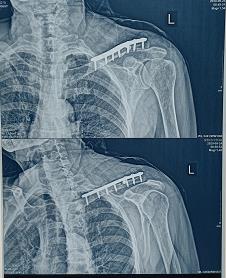

3.郑州市骨科医院影像诊断报告单(2021.04.01):左侧锁骨骨折术后,断端复位佳,金属内固定;关节结构可。

4.郑州市骨科医院SCT影像诊断报告单(2021.04.01):左侧第2-7肋骨折线模糊,对位尚可。

被鉴定人张某某左锁骨粉碎性骨折术后;左肩侧胛骨骨折。查体:左侧肩锁部见一长12cm瘢痕。左肩关节活动度正常,同对侧。阅片示:左侧肩胛骨见骨折影,断端位置可。左侧锁骨骨折术后,断端复位佳,金属内固定;关节结构可。参照最高人民法院、最高人民检察院、公安部、国家安全部、司法部联合发布《人体损伤致残程度分级》,被鉴定人张某某左肩锁部损伤不构成伤残。

2、关于肋骨损伤